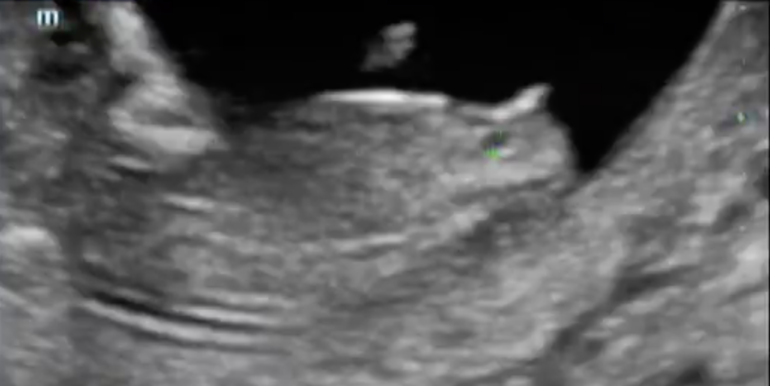

Мы были на первом скрининге, познакомили папу с малышом :) В 12,3 дня КТР был 59,3 мм. Носовая косточка 2,8 мм. ТВП 1,0 мм. Вес 53 гр. Теперь ждем результаты крови (НИПТ), и точно узнаем пол. Врач предположил на 65 процентов девочку (фото бугорочка ниже).

Наш бугорочек:

Чёт как-то не сильно на девочку похож бугорочек 🙈 У нас 12+4, рядышком топаем))))

Юль, это как раз на девочку=))) У нас так же=) Лежачая штука-типа будущий клитор))

Я видела эту картинку. Но вот девчонки выставляли, кому сказали про мальчиков, там такое же))))) И у них он смотрит вверх)))) я видела ещё и другие картинки, что под углом 30 градусов к позвоночнику - это уже мальчик. Время покажет)))))) Я и не надеюсь что-то узнать на скрининге завтра, проходим в обычной ЖК.

Мой узист (к слову, один из лучших в нашем городе) измерял вообще не углом, а по расстоянию от бугорка до копчика. Сказал что у девочек это расстояние меньше 7,6 мм, а у мальчиков - больше. у нас 7,1 мм.

Скоро узнаем, работает ли это так